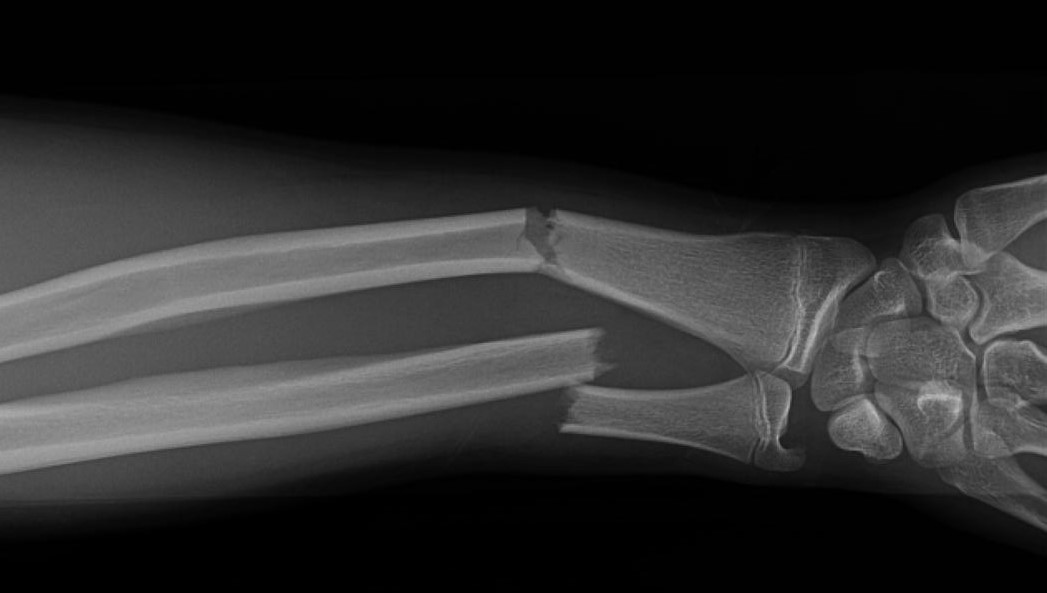

Você já teve uma fratura exposta? Já viu em outra pessoa? Aposto que naquele momento, ninguém parou para observar a beleza branca do osso exposto, nem para admirar a elegância da estrutura óssea, muito menos para ponderar a perfeição do esqueleto humano. Naquela hora, talvez alguns desmaiaram, outros ligaram para o hospital, certamente alguém gritou, mas ninguém disse, “que osso bonito você tem!”.